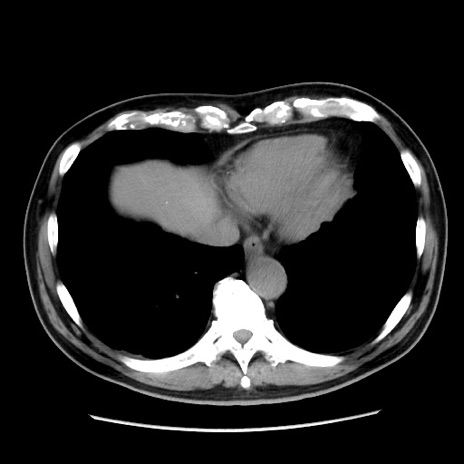

症例16(横断像)

【症例】 70歳代男性

【主訴】 腹痛、嘔吐

【現病歴】 約1ヶ月前より間欠的に腹痛と嘔吐あり、当院消化器内科を受診したところCTで多発する肝臓のLDAを指摘され、精査中であった。以降は消化器症状は安定していたが、2日前より嘔気と腹痛があり、同日より排便・排ガスが消失した。改善認めず、 本日、救急外来を受診した。

【既往歴】 大腸ポリープ切除後。

【身体所見】意識清明・会話良好、BT 36.3℃、BP 127/80mmHg、 P 80bpm、腹部:膨満あり、平坦・軟、上腹部正中および下腹部正中に圧痛あり、反跳痛なし、筋性防御なし。

【データ】WBC 7200、CRP 0.77